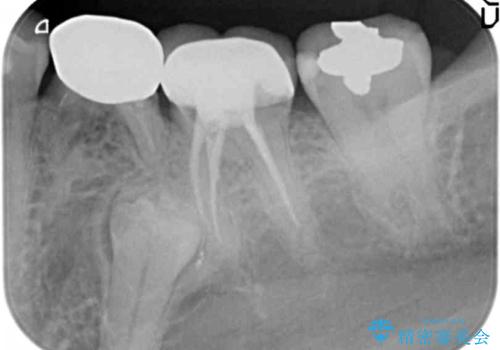

- 大人になってからも残っていた乳歯が揺れ始め、抜歯を覚悟しインプラント治療を希望して来院されました。

X線写真より、乳歯は抜歯が必要な状態でインプラントは小臼歯の埋伏により難しい状況であったのでブリッジによる補綴を選択しました。

ブリッジ治療の予知性を高めるために、虫歯の徹底的な除去に加え縁上歯質を確保するための歯周外科手術、マイクロスコープを用いた精密根管治療を行う治療計画としました。